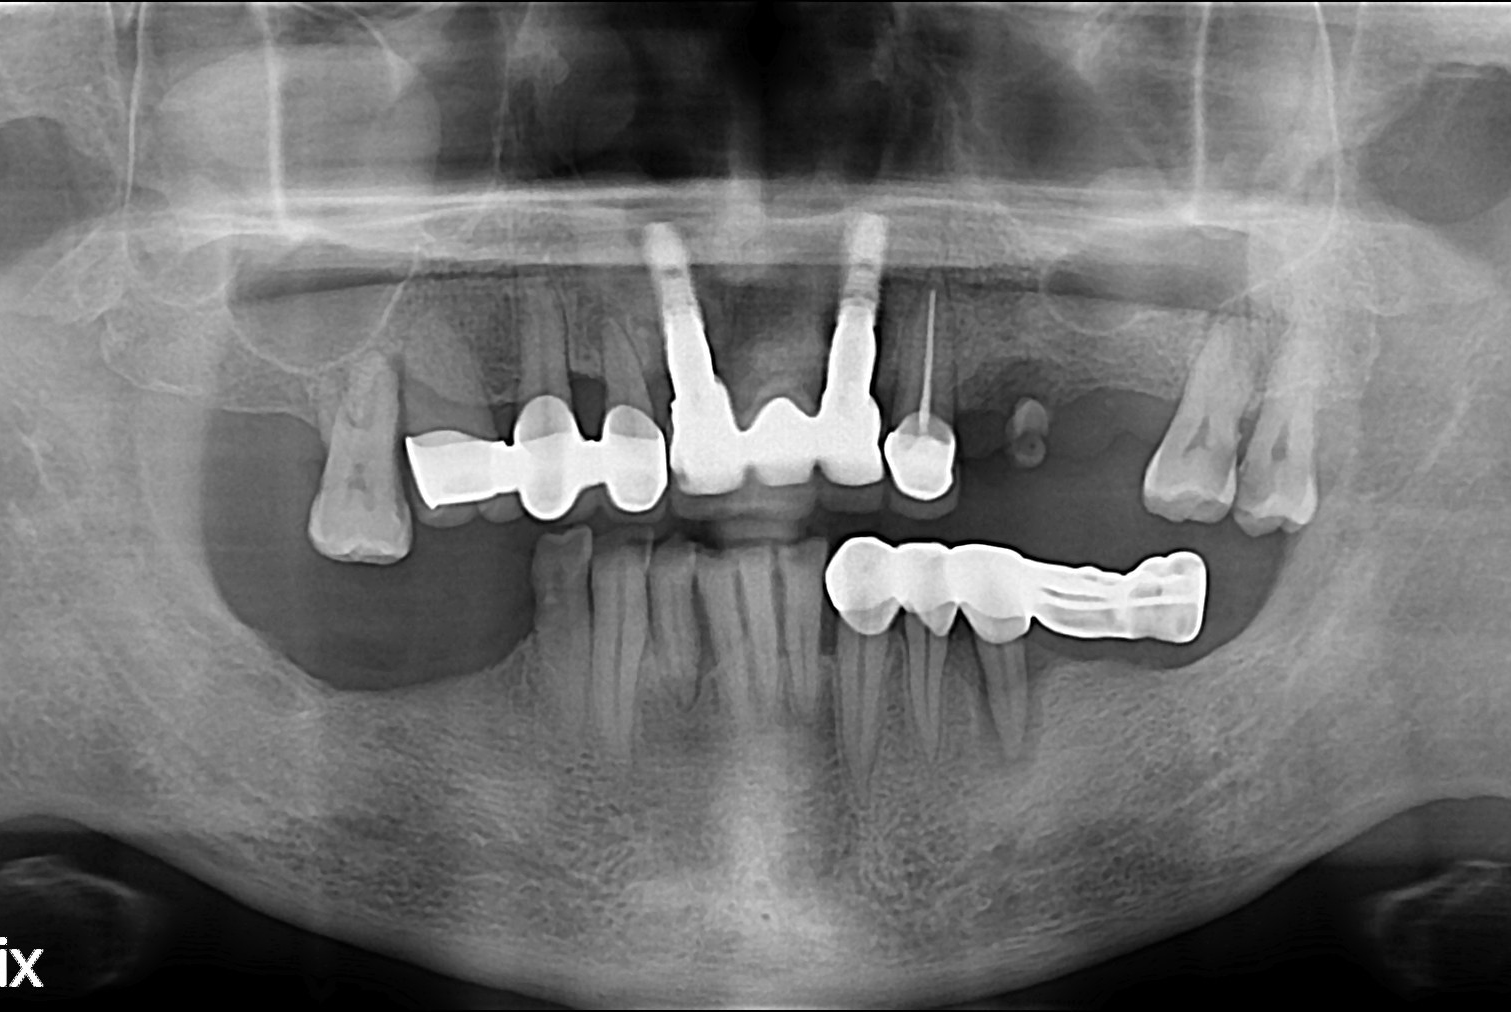

치료전 : 2019-09-05

정철호 후.jpg

치료후 : 2019-12-04

세종치과는 많은 환자와 다양한 케이스를 바탕으로 항상 편안한 임플란트 수술을 제공하고자 노력하고,

오래동안 튼튼히 쓸 수 있는 임플란트 수술을 가장 큰 목표로 삼고 있습니다